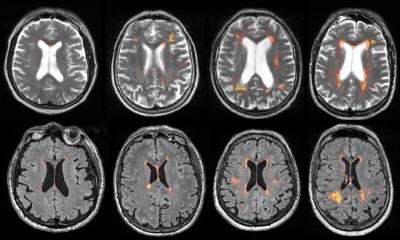

Ils sont très courants chez les personnes âgées et sont liés à une pensée plus lente dans la vie quotidienne, par exemple. Sur la base des données de plus de 2800 participants à l’étude à l’âge de 65 ans, Frauke Beyer du Max Planck Institute for Cognitive and Neurosciences (MPI CBS) à Leipzig, en Allemagne, et Stephanie Debette de l’Université de Bordeaux en France, où de telles lésions se produisent dans le cerveau et comment elles sont liées à des accidents du trait et au démentie.

Les chercheurs présentent leurs résultats dans le journal «Alzheimer’s & Dementia».